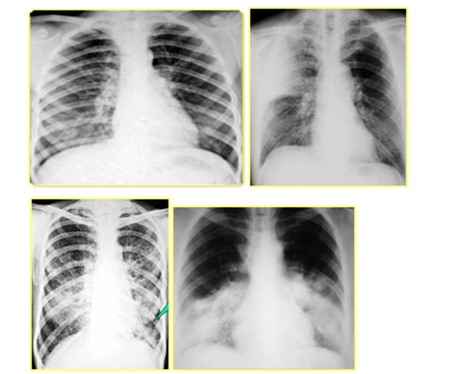

二、肺部感染

肺部感染=咳嗽、咳痰(间质性肺炎无痰)+发热+白细胞增高,中性粒细胞比例增高

| 肺部感染类型 | 特点 |

| 小叶性肺炎(支气管肺炎) | 两肺中下野散在斑片影 |

| 大叶性肺炎 | 大片致密影 |

| 间质性肺 | 网状或小结节状影 |

| 传染性非典型肺炎 | 不同程度的片状、斑片状浸润性阴影或呈网状改变,进展迅速者呈大片状阴影 |